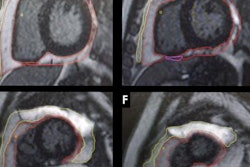

Noncalcified coronary plaque in an asymptomatic 52-year-old man living with HIV with a 10-year Framingham risk of 5%. Images show 256-section contrast-enhanced coronary CT angiography with electrocardiographic gating and curve reformat. (A, B) CT scan shows a smooth noncalcified plaque in the right coronary artery (arrows) with 70%-80% stenosis. (C, D) The right coronary artery plaque volume was 130 mm3 (green lines).In part due to antiretroviral therapy, people with HIV are living longer and thus may experience age-related conditions such as coronary artery disease, the group wrote. Studies have suggested that they have a greater risk of heart attack than people who aren't infected, but the reasons for this are unclear. Inflammation and immune dysfunction could play a role.